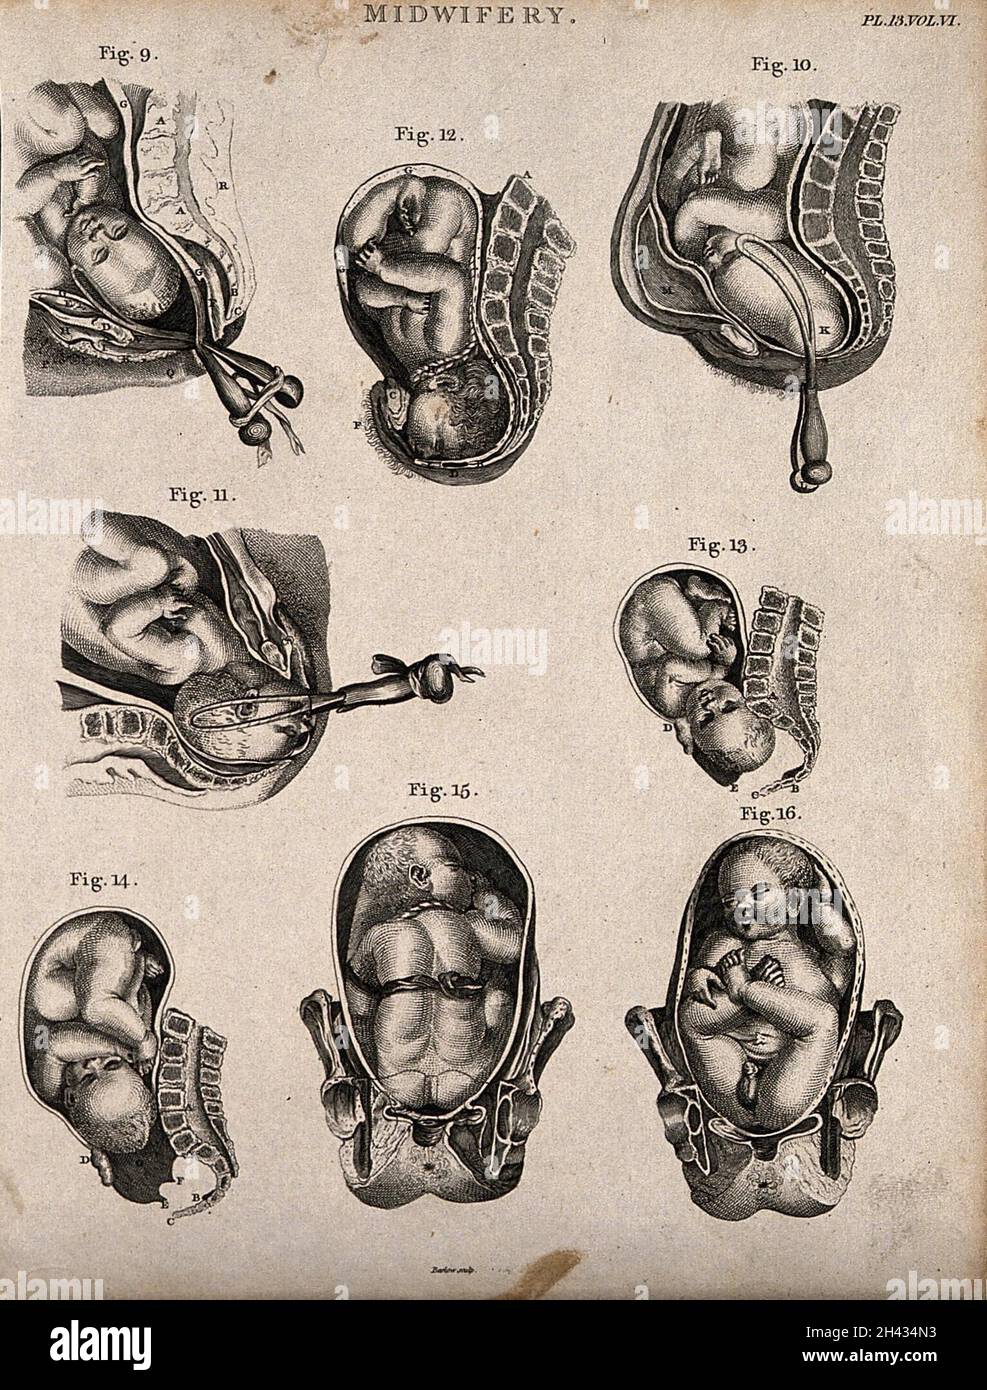

Eight diagrams illustrating babies in the womb in different positions about to enter the world. Etching by Barlow. Stock Photohttps://www.alamy.com/image-license-details/?v=1https://www.alamy.com/eight-diagrams-illustrating-babies-in-the-womb-in-different-positions-about-to-enter-the-world-etching-by-barlow-image449997775.html

Eight diagrams illustrating babies in the womb in different positions about to enter the world. Etching by Barlow. Stock Photohttps://www.alamy.com/image-license-details/?v=1https://www.alamy.com/eight-diagrams-illustrating-babies-in-the-womb-in-different-positions-about-to-enter-the-world-etching-by-barlow-image449997775.htmlRM2H434N3–Eight diagrams illustrating babies in the womb in different positions about to enter the world. Etching by Barlow.